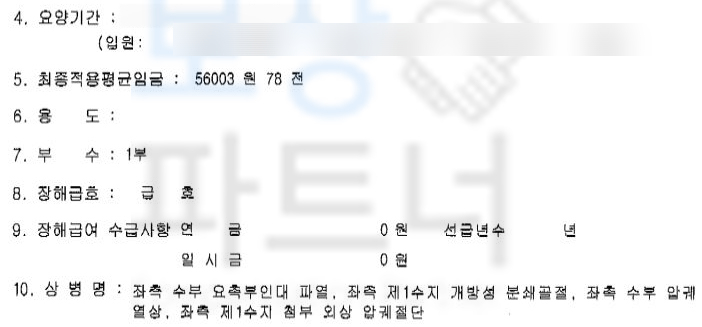

먼저 근무 중 다치신 재해이기에 산재보험에서 보상받으실 수 있습니다. 많은 분들이 병원 원무과의 도움으로 산재 최초요양 신청서를 작성해서 무리 없이 산재 요양 승인을 받으시는데요,

문제는 산재 요양 이후 장해급여입니다.

장해급여는 주치의의 장해 소견서가 필요한데 대부분의 주치의는 자신이 치료한 환자에게 장해 진단을 내리기 쉽지 않을뿐더러 공단에서의 조사 과정도 있기 때문에 쉽지 않죠. 하지만 차@@님은 보상 파트너에 상주하는 노무직원을 통해 산재 장해급여 청구를 위임해 주셨고 산재 장해판정을 함께 진행한 결과

산재 장해등급 13급!!** 일시금 99일**의 총 장해급여 5,544,297원입니다. 보험사에 후유장해보험금 청구를 위해서는 의료 전문의의 후유 장해 진단서가 필요합니다.